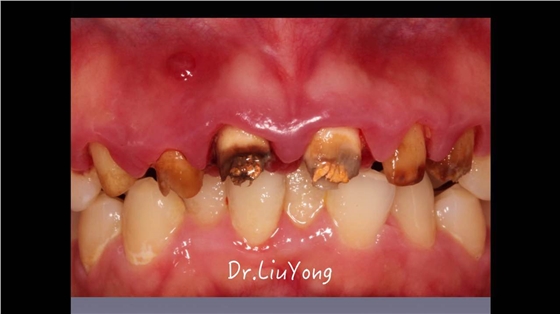

嚴重破壞生物學寬度,根尖瘺管,重行根管治療,第一次冠延長建立唇腭側及鄰面BW, 術后牙齦扇貝形差,齦乳頭黑三角,再次行美學冠延長,建立牙齦扇貝形,手術免費, 患者因經濟原因只能選擇鑄樁及鈷鉻合金烤瓷冠。終于完工